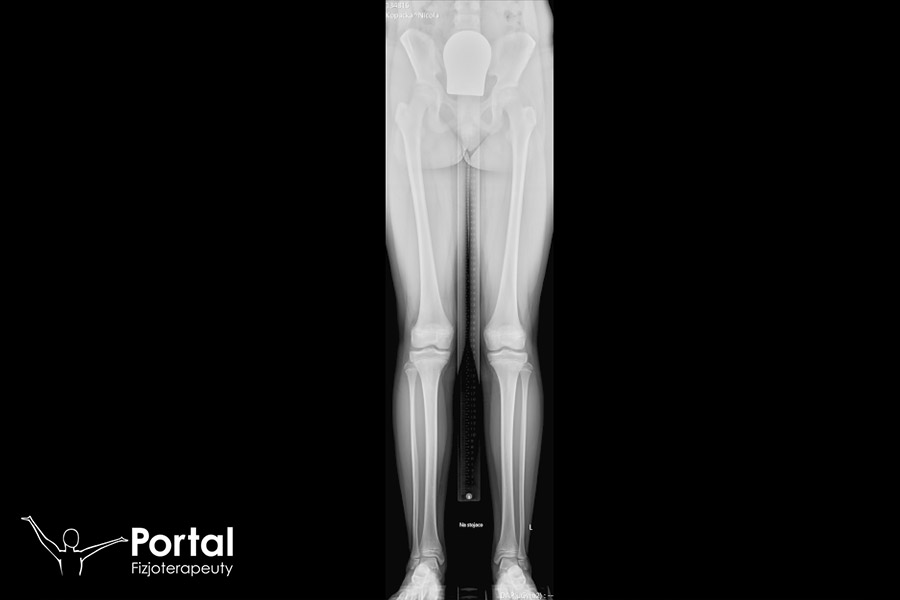

RTG pomiarowe kończyn dolnych to metoda badania radiologicznego, uwidoczniająca całą długość kończyn dolnych od kości miednicznych, aż do kości palców